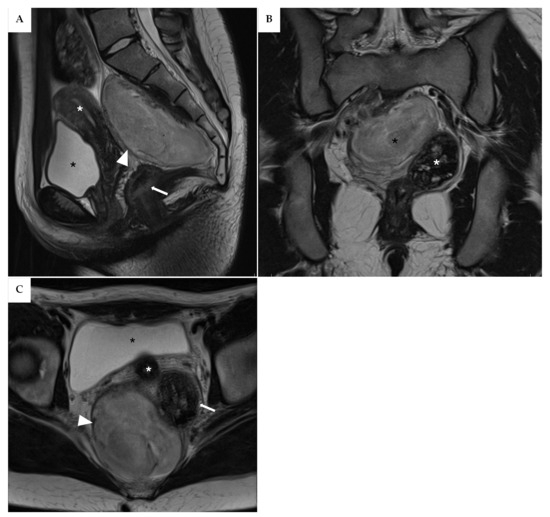

An 18-year-old woman presented to our clinic in March 2024 after undergoing pelvic contrast-enhanced Magnetic Resonance Imaging (MRI) the previous month on the recommendation of her gynecologist. The patient had been experiencing dysmenorrhea for the past two years and sought consultation to start contraceptive therapy. During an ultrasound examination, an incidental mass was detected, initially suspected to be an ovarian cyst. However, the MRI revealed a sacrococcygeal mass measuring approximately 106 mm × 77.4 mm × 49.8 mm, extending from S1 to the coccyx (Figure 1A–C). The differential diagnosis included neurofibroma, teratoma, and myelolipoma.

Figure 1. (A) Mid-sagittal TSE T2-weighted image. A voluminous mass is visible in the presacral space, extending from S1 to the coccyx (white arrowhead). There is initial compression of the rectum without associated clinical symptoms (white arrow), as well as mild compression of the uterus (white asterisk). The bladder shows no involvement (black asterisk). (B) Coronal TSE T2-weighted image. The presacral mass (black asterisk) appears to have a well-defined border on the left side, while on the right side it is not clearly distinguishable. White asterisk: rectum. (C) Axial TSE T2-weighted image. The presacral mass (white arrowhead) is in contact with the rectum (white arrow), with no clear cleavage plane visible on imaging; however, a plane of separation was fortunately identified during surgery. White asterisk: uterus. Black asterisk: bladder.